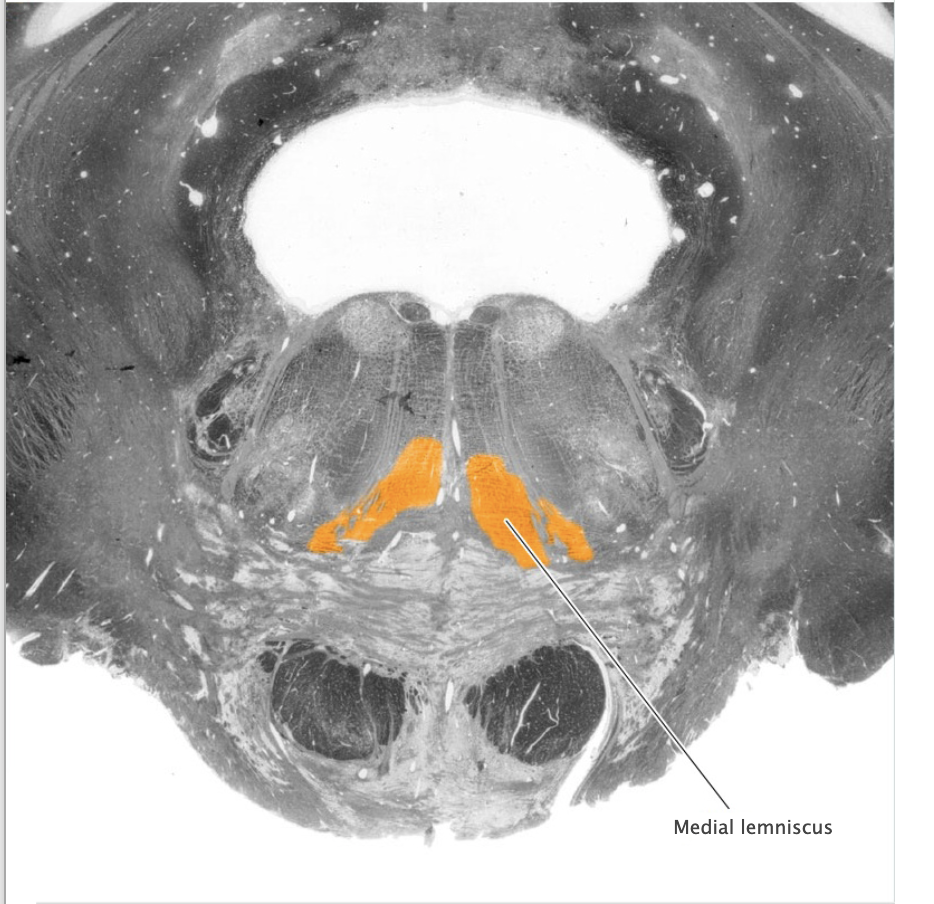

Dorsal column-medial lemniscal system

Ascending somatic sensory pathway that conveys tactile and proprioceptive information for the body and posterior third of the head.

Dorsal column nuclei

Gracile nucleus and cuneate nucleus; contain the second-order sensory neurons that relay mechanosensory information from peripheral receptors in the body (excluding the face) to the thalamus via the medial lemniscus. The dorsal column nuclei are located in the lower medulla.